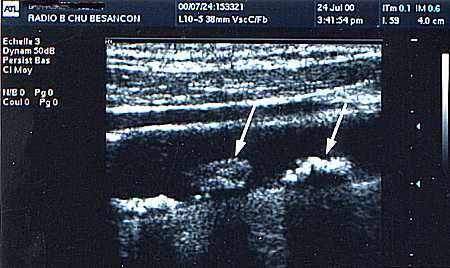

Placa de aterom calcificat pe carotida comuna distala.

Ecografie mode B.